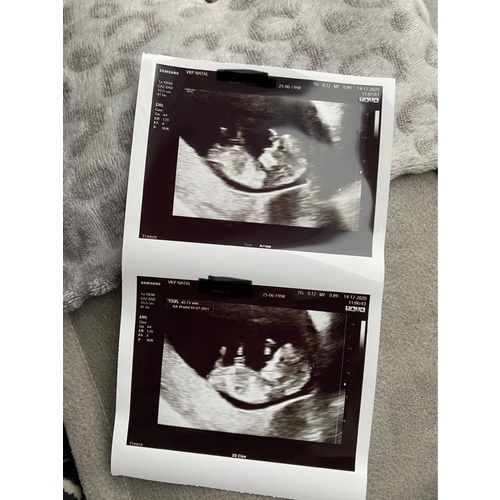

Dit was met precies 11 weken, je ziet echt al een heel mensje 💖